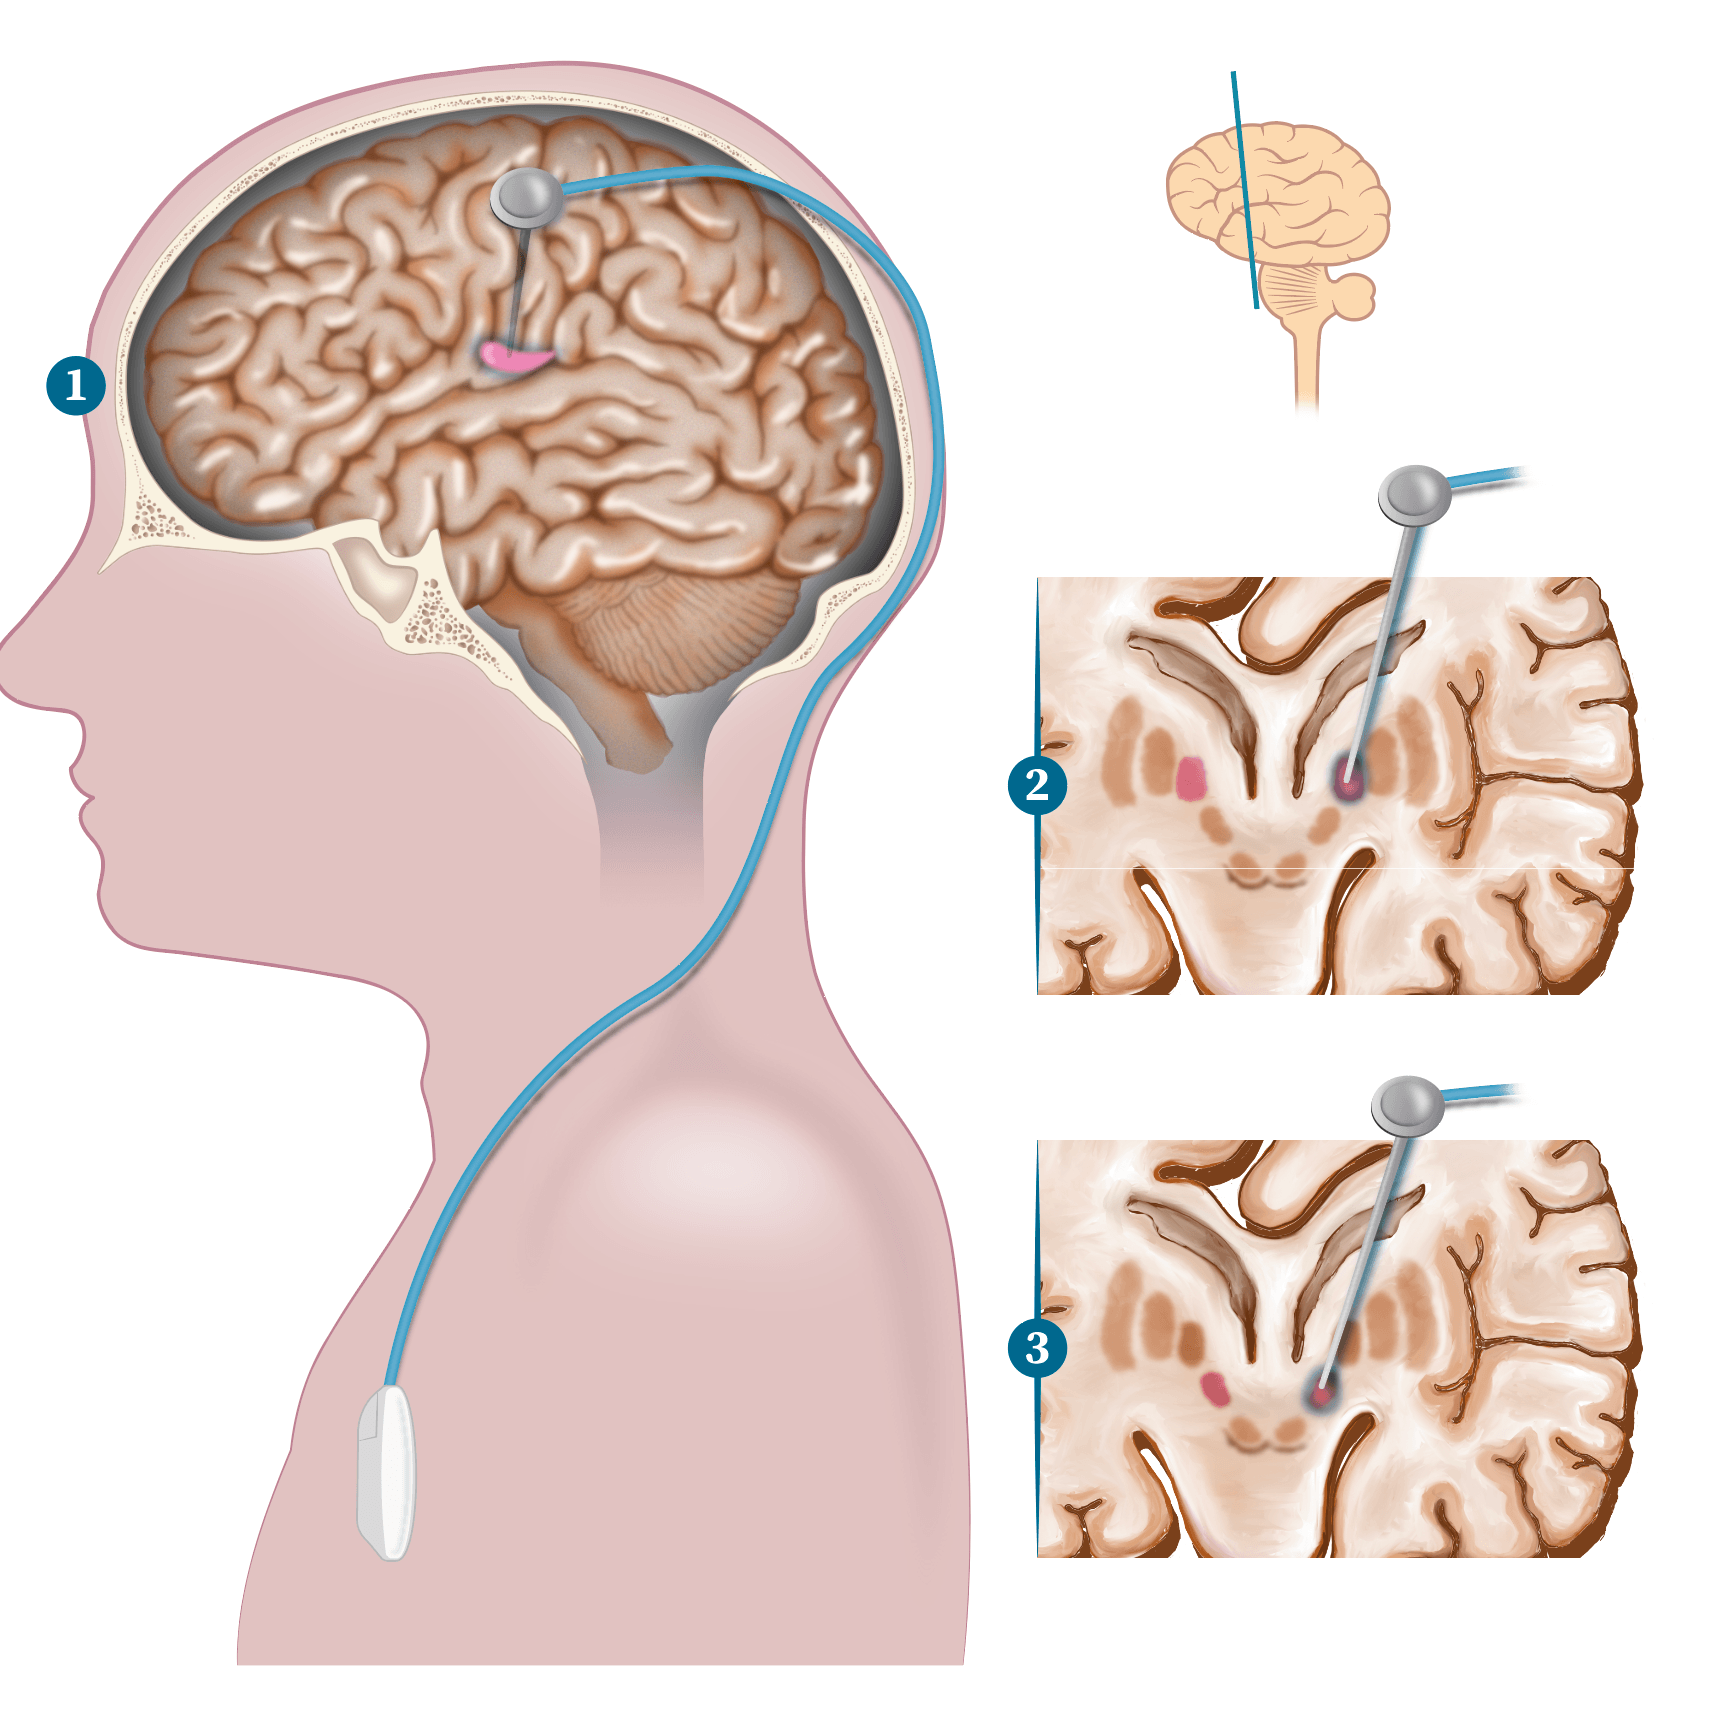

Ilustración Medica / Neurología

Neurología